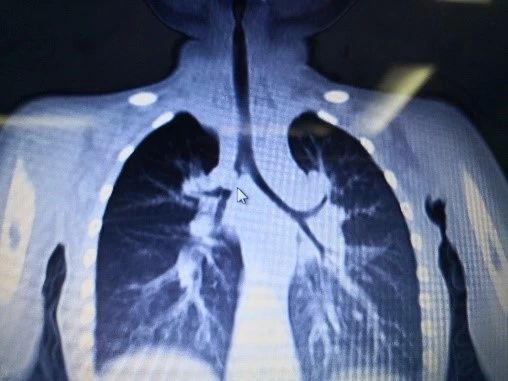

傍晚我们接到病房电话,有个气道异物史不明的一岁患儿晚上要来做手术。我们赶紧到病房了解了患儿的病史。家长诉患儿3周前反复咳嗽,在外院拍片示右侧肺炎住院治疗。一周前复查胸部CT发现,右侧支气管异物。值得注意的是,家属诉未发现明显异物呛咳史。 (患儿术前胸部CT) 气道异物术前评估、病史体征非常重要: 1.异物史: 位置、大小、留存时间、 异物种类 2.听诊及评估呼吸系统并发症:上呼吸道感染、肺炎、哮喘,肺气肿、肺不张、肺炎、气道高敏 3.有无异物史:患儿可能是肺炎,哮喘,喉炎...... 4.麻醉方案的选择: 保留呼吸还是控制呼吸?